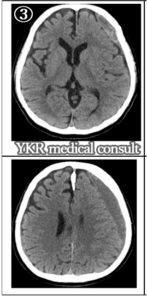

③血腫は減少傾向だが、左側頭頂部には水平断で24mmの厚さで血腫が存在している。

慢性硬膜下血腫の経過について、長期間にわたり、程度の差はあるものの、左前頭頭頂部を中心に圧迫が持続しており、交通事故後約1年の時点でも左側血腫はまだ厚い状態であった(画像③参照)。